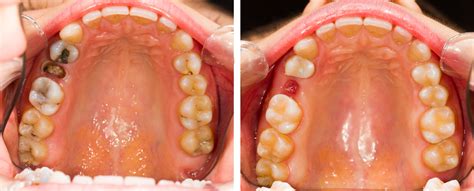

Estos dientes suelen aparecer entre los 17 y los 25 años de edad, aunque algunas personas nunca desarrollan las muelas del juicio. Muchas personas sufren la impactación de las muelas del juicio. Esto se produce cuando las muelas del juicio no tienen suficiente espacio para erupcionar en la boca o para desarrollarse normalmente.

Como dentista, a menudo recomiendo la extracción de las muelas del juicio cuando veo indicios de estos problemas o riesgo de que ocurran. Cada caso es único: a veces quitamos las cuatro cordales de forma preventiva, y otras veces solo cuando dan molestias. Si tus muelas del juicio están sanas, bien posicionadas y no causan inconvenientes, es posible que no sea necesario extraerlas inmediatamente; bastará con un control periódico.

Sin embargo, si tu odontólogo te sugiere quitarlas, suele ser para prevenir consecuencias peores en el futuro. Si se dejan muelas del juicio problemáticas sin extraer, podrían empeorar: infecciones más serias, daño permanente en el diente de al lado o tratamientos más complejos más adelante.